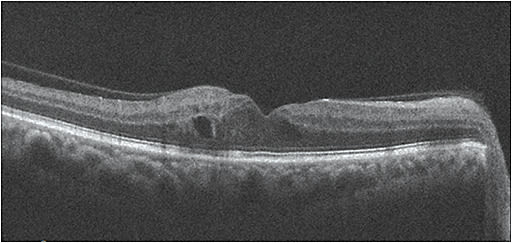

That said, while retinal photography may serve as a screening tool for retinopathy, it is not a substitute for a comprehensive eye exam, according to the ADA statement. - SD-OCT. This should be performed routinely on all patients who have diabetes, the ADA statement says. It aids in detecting DME, specifically center-involved DME. SD-OCT has become the standard to quantify retinal thickness, monitor DME and respond to treatment.

The ADA statement recommends monthly anti-VEGF agents for central-involved DME (macular edema involving the center of the fovea of the macula), as serial injections of these agents reduce macular edema, preserving or improving vision for patients who have DR. Thus, these patients should be co-managed with a retinal specialist. Also, anti-VEGF therapy has recently been shown as an effective treatment for proliferative DR.